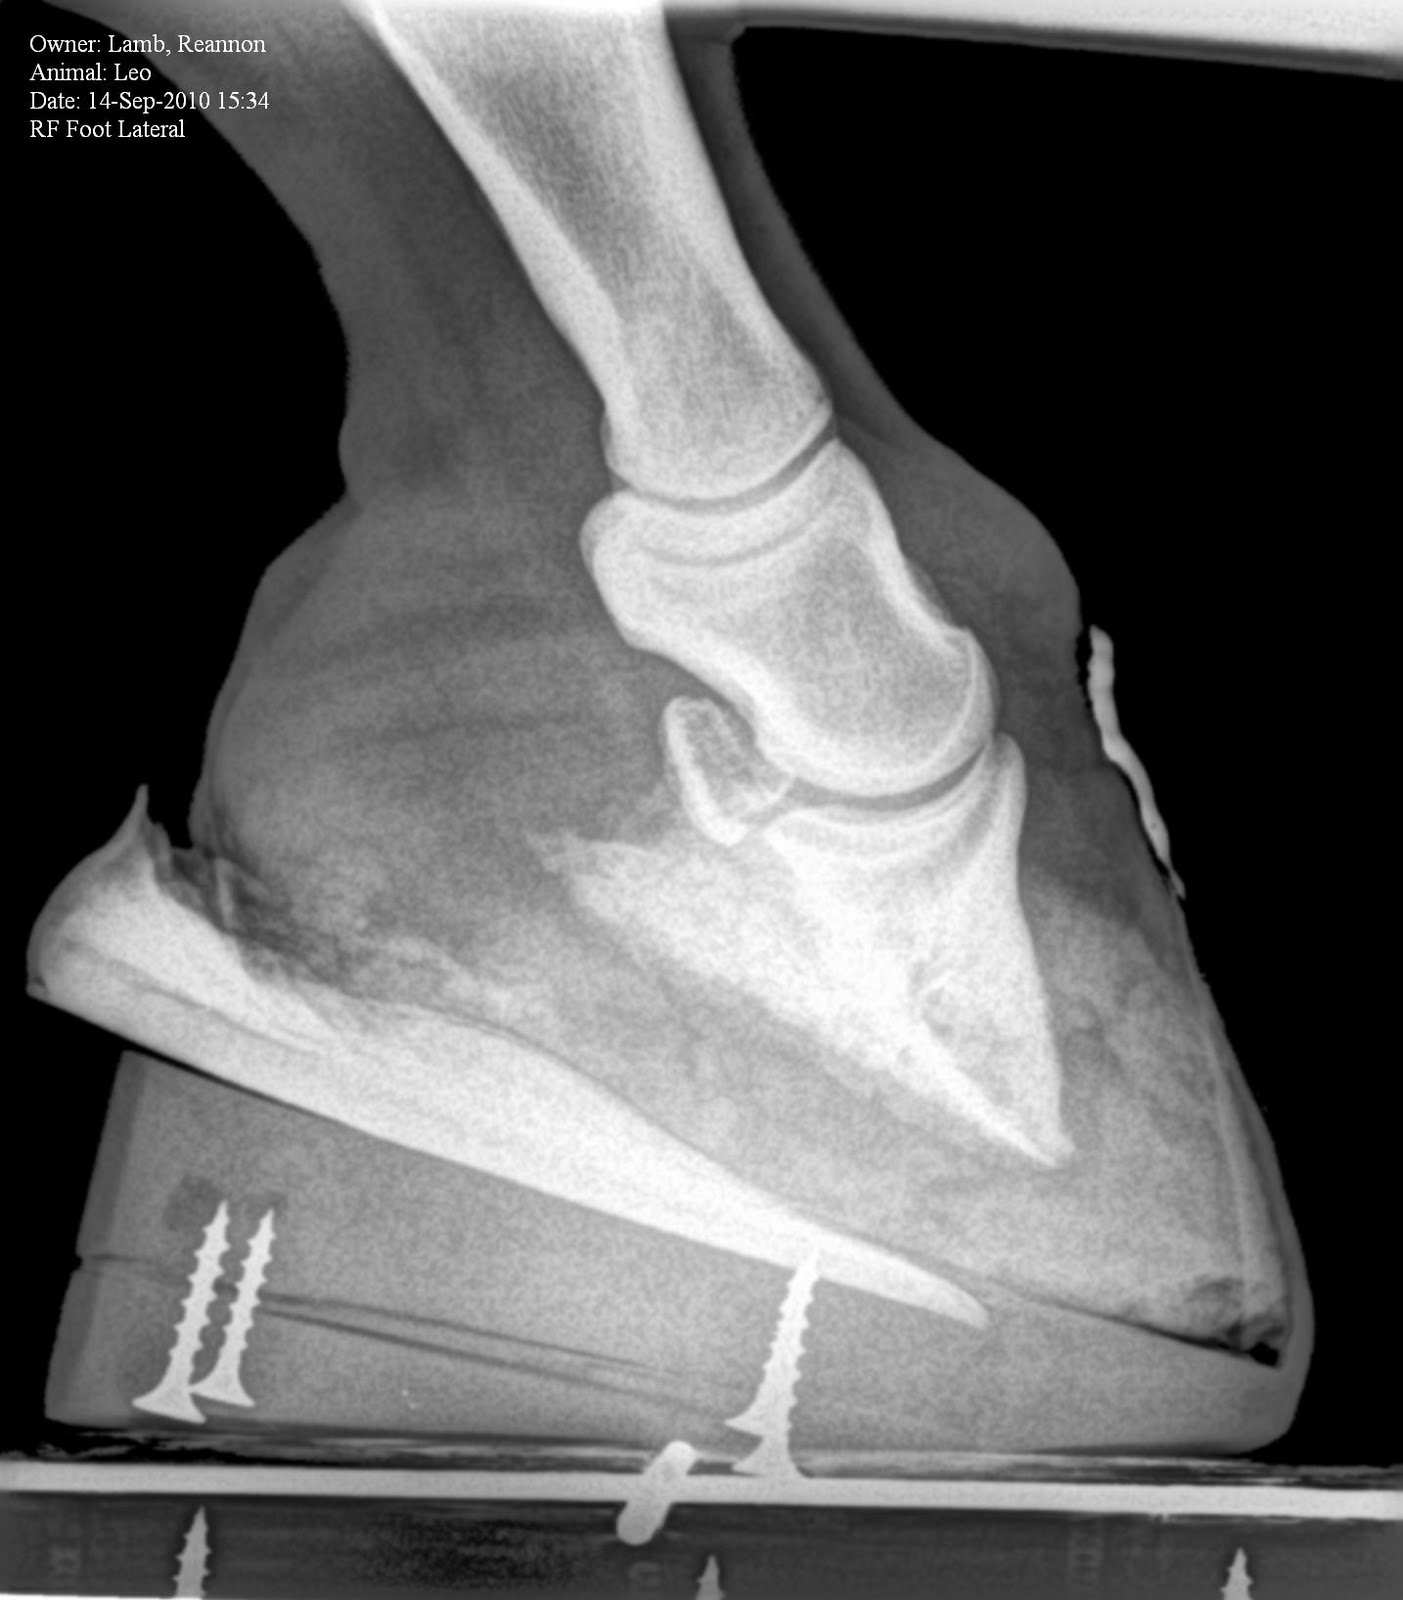

Horse Founder X Rays . founder in horses, also called laminitis, is the profound swelling and pain in the hoof when. radiographic studies are an essential. This can reveal underlying causes like metabolic disorders that can predispose a horse to founder. These can show any rotation or sinking of the coffin bone inside the hoof, providing a clear picture of the severity of the founder.

radiographic studies are an essential. These can show any rotation or sinking of the coffin bone inside the hoof, providing a clear picture of the severity of the founder. founder in horses, also called laminitis, is the profound swelling and pain in the hoof when. This can reveal underlying causes like metabolic disorders that can predispose a horse to founder.

Founder Info for Horse Owners! Leo's Radiographs (aka xrays) Horse Founder X Rays These can show any rotation or sinking of the coffin bone inside the hoof, providing a clear picture of the severity of the founder. founder in horses, also called laminitis, is the profound swelling and pain in the hoof when. This can reveal underlying causes like metabolic disorders that can predispose a horse to founder. radiographic studies are. Horse Founder X Rays.

Founder Info for Horse Owners! Leo's Radiographs (aka xrays) Horse Founder X Rays This can reveal underlying causes like metabolic disorders that can predispose a horse to founder. founder in horses, also called laminitis, is the profound swelling and pain in the hoof when. These can show any rotation or sinking of the coffin bone inside the hoof, providing a clear picture of the severity of the founder. radiographic studies are. Horse Founder X Rays.

Founder Info for Horse Owners! Leo's Radiographs (aka xrays) Horse Founder X Rays radiographic studies are an essential. This can reveal underlying causes like metabolic disorders that can predispose a horse to founder. These can show any rotation or sinking of the coffin bone inside the hoof, providing a clear picture of the severity of the founder. founder in horses, also called laminitis, is the profound swelling and pain in the. Horse Founder X Rays.